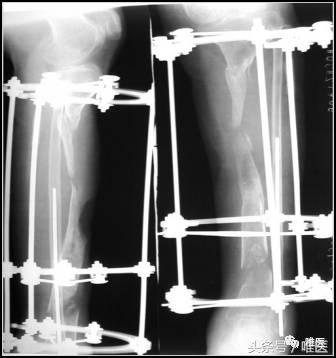

3. X线片示

左胫骨中上段节段性骨缺损,断端骨质长节段萎缩,骨质硬化。

一期:左胫骨全环外架固定,远端截骨,术后骨段逐渐滑移,克服骨缺损。